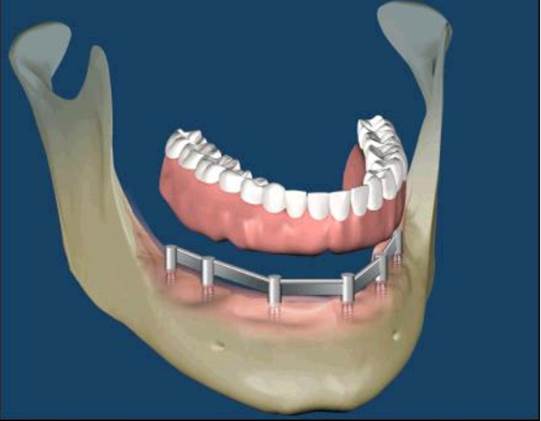

All-on-Fou/Six

近年來由於人工植牙的技術普及,患者大都知道植牙可做固定式假牙,但同樣的有時患者因為身體、經劑因素等受限,也可以考慮植入幾支人工植牙,再完成固定可撤式活動義齒,這樣可讓活動式假牙的固定性有效加強。通常上顎可用6支植體,下顎則4-5支植體固定,如需更穩定的受力,亦可再增加植體數目。(圖52-55)

圖52

圖53

圖54

圖55

參考病例: 固定式植牙牙橋&固定可撤式活動義齒